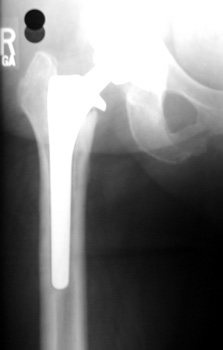

SUBSIDENCE - loose femoral prosthesis with interface widening,

osteolysis Gruen zone 6, cement fracture left femoral component

and osteolysis, with femoral component in valgus.